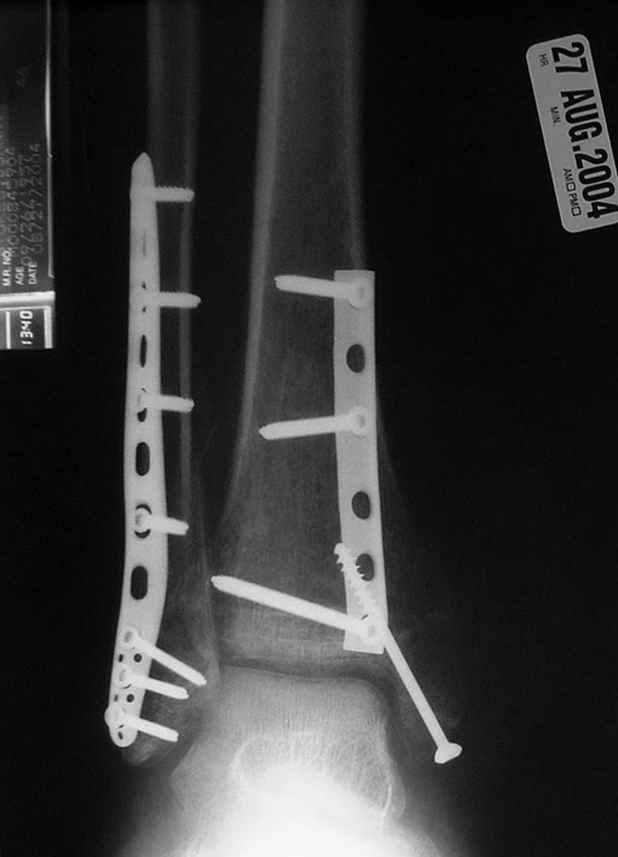

Второй случай сделан из одного разреза

ЕЧ LISS plate, mininvasive approach - luxurous !

Вопрос практического характера - такой подход рутинный или при определенных показаниях и каких? Спрашиваю потому, что при потоке больных - закрытая голень, бедро, голеностоп и т.д. лучевая нагрузка должна быть немалая, каковы показатели дозиметра после такого операционного дня и при 2-3 операционных днях в неделю по 5-6 случаев (не считая ургентностей)?

С точки зрения : Сгорая сам - свети другим :-)) это вполне понятно, но личная практика показывает, что далеко не все пациенты относятся волнительно и критично к длине кожного разреза. Подозреваю, что это и есть критерий при выборе техники фиксации?

На прямой проекции послеоперационного Рг макроскопически все выглядит очень анатомично, при микроскопическом ( :-)) ) рассмотрении можно все-таки заметить вальгизацию тарана, суставная щель в латеральном отделе сустава несколько уже , чем в медиальном при отсутствии латерального смещения тарана. У меня был аналогичный случай (без LISS , без мини доступа) с вальгусным наклоном тарана при восстановленном ankle mortise при последовательном наблюдении с интервалами в 6-8 недель в послеоперационном периоде отмечалось прогрессирующее сужение суставной щели в латеральном отделе сустава, закончившееся посттравматическим ОА, к счастью боли умеренные, купируемые аналгетиками или своими эндорфинами:-))(активная пациентка, у которой нет времени на болезни....) Какова жизненная ситуация в приведенном вами случае? И последнее, что я хотел бы прояснить для себя - фиксация внутренней лодыжки: я обычно комбинирую фиксацию компрессирующим винтом со спицей - по идее ротационная стабильность должна быть лучше, чем один винт, каковы ваши наблюдения в этом плане?

За последнее 10-12 лет после стабилизации малоберцовой кости, стали применять более усовершенный, сложный, хорошо вам известный метод

Илизарова (кстати наряду с тибиал плато, пилон является одним из показанием по применению аппарата Илизарова при травмах) или Hybrid

Fixator, из минимальных доступов комбинированный метод для восстановления суставной поверхности-фиксация каннулированными

шурупами, создания жесткой системы фиксации до сращения перелома, защита от вальгусной деформации и на место образовавщегося метафизарного дефекта- костная пластика ауто костью или его

синтетические заменители, это сегодняшная тактика лечения.